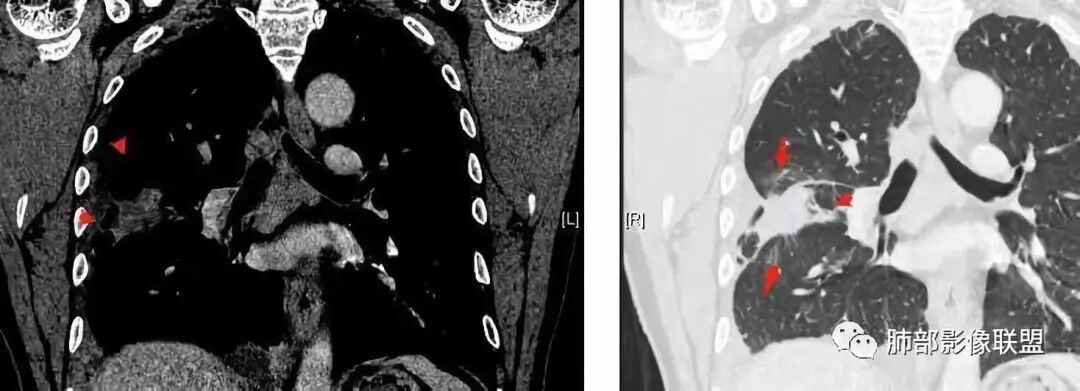

南边:大家看看前纵隔的病灶,符合肿瘤吗脂肪,周围密度增高

三个石头:比较散;像炎症的蔓延生长南边:是,这些看着心里不踏实觉得把这个纳入肿瘤去考虑是否合适总觉得边缘收缩的、散在的朝周围蔓延;中央还跨过脂肪,朝对侧胸膜蔓延把这个与囊性病变连到一起去考虑是否还需要斟酌一下因为这个就方向差异大了南边:连在一起,囊实性,边界不清,自然考虑恶性:如果独立,囊张力高、边界清楚,间隔,自然朝良性考虑:

大家仔细看看积液中的游离气体;

不是支气管,是积气;是穿刺进去的;

囊内密度不一致

我认为囊张力高,积液中的气体均在周围,外侧、下方,囊内有间隔:各腔密度不一致;提示:囊腔属于前纵隔,不是包裹性积液;现在的问题:囊腔与内侧的病灶是否是一体的

南边:我总觉得这个纵隔内不像是一个肿块的改变,扁平,周围蔓延:有符合炎性的的特点,或者肿瘤的侵犯;但是肿瘤的侵犯,不大符合,实性部位的边缘过于柔和,没有毛糙的侵犯边缘。

肺内结节,近端支气管堵塞狭窄

整体边缘收缩,部分膨隆

炎性要考虑,但恶性不能排除